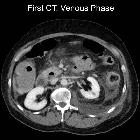

Necrotizing

pancreatitis: peripancreatic necrosis alone. Acute necrotic collections (ANCs), affecting retroperitoneal spaces: left anterior pararenal space and lower extension until iliac fossa, affecting left paracolic gutter, posterior pararenal space and left psoas muscle.